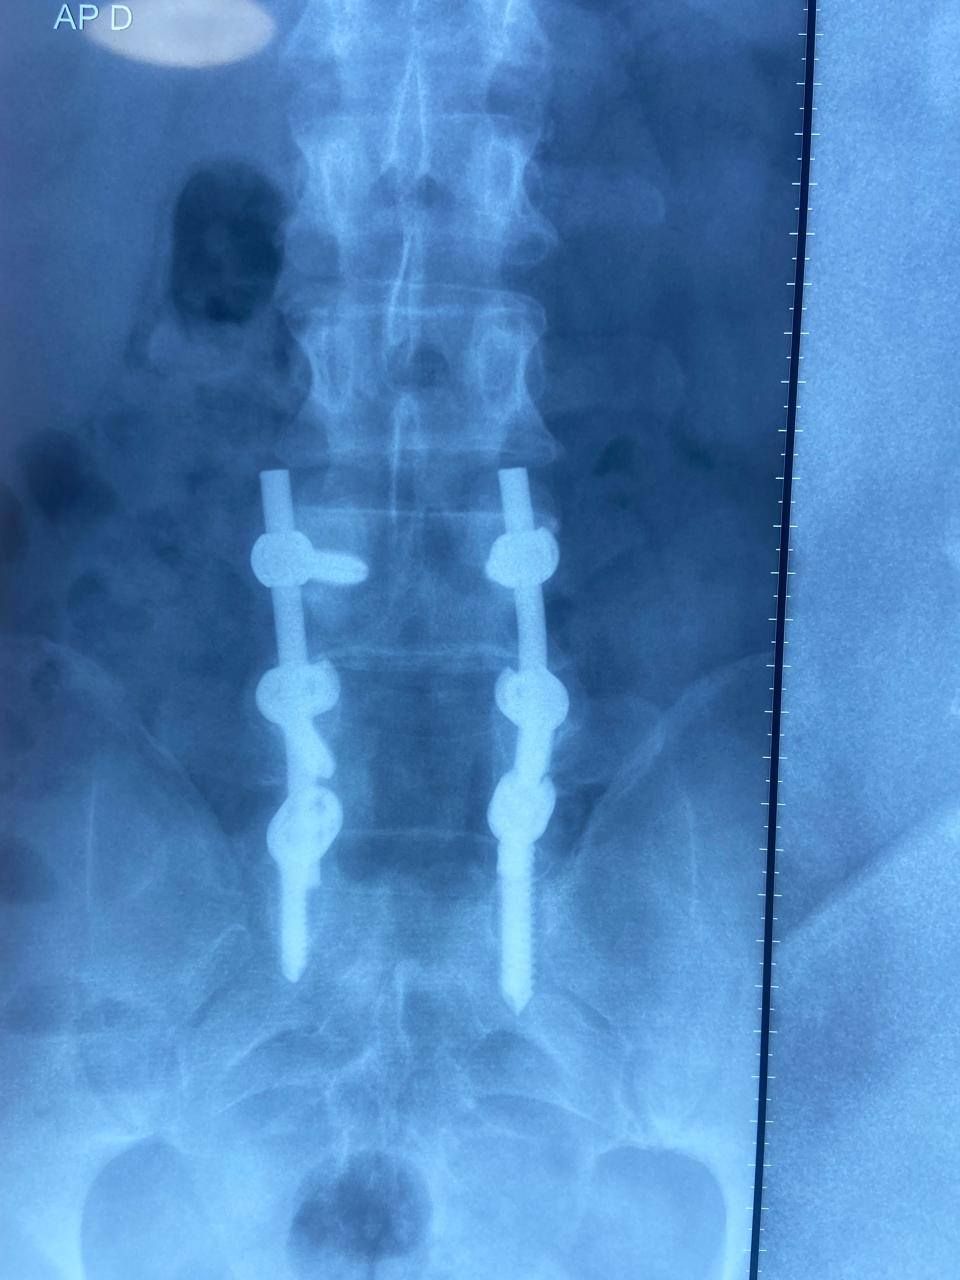

Neurocirugía general, cirugía de epilepsia, instrumentación de columna, cirugía funcional.

• Cirugía de columna

• Cirugía de columna mínimamente invasiva

• Cirugía de deformidades de la columna